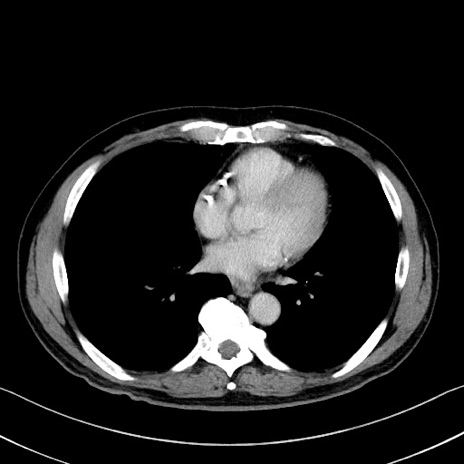

症例35(横断像)

【症例】70歳代 男性

【主訴】腹部膨満、嘔吐

【現病歴】昨日より腹部膨満感出現。本日増悪し、仙痛出現。嘔吐あり、受診。

【既往歴】糖尿病、胆摘後

【身体所見】BP 149/80mmHg、HR 74/min、BT 35.9℃、腹部:膨満、軟、圧痛なし。腸雑音減弱あり。上腹部正中切開瘢痕あり。

【データ】WBC 13500、CRP 1.72